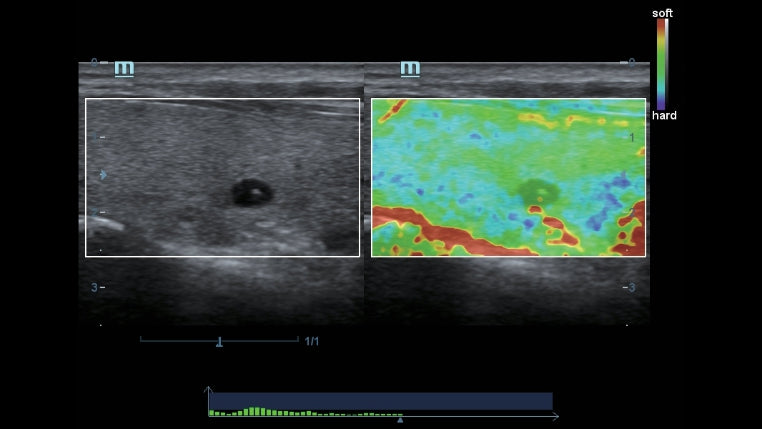

Como una solución de obstetricia, ginecología e imagen general completa, proporciona una interfaz muy robusta e intuitiva. Supera las expectativas de tus rastreos con su sistema de transductores pure crystal